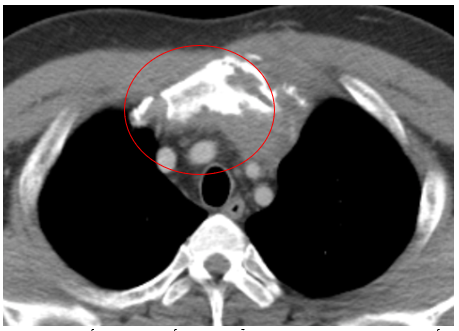

Case lâm sàng: Ứng dụng trí tuệ nhân tạo (Artificial intelligence – AI) trong chẩn đoán và điều trị sớm Ung thư phổi tại Trung tâm Y học hạt nhân và Ung bướu, Bệnh viện Bạch Mai

Theo GLOBOCAN 2022, ung thư phổi đứng đầu về số ca mới mắc (2.480.301 ca mới mắc chiểm 12.4%) và dẫn đầu số ca tử vong (1.817.172 ca tử vong chiếm 18.7%) trên toàn thế giới.  Tại Việt Nam tỷ lệ mắc ung thư phổi xếp thứ ba 13,5% lệ tử vong...